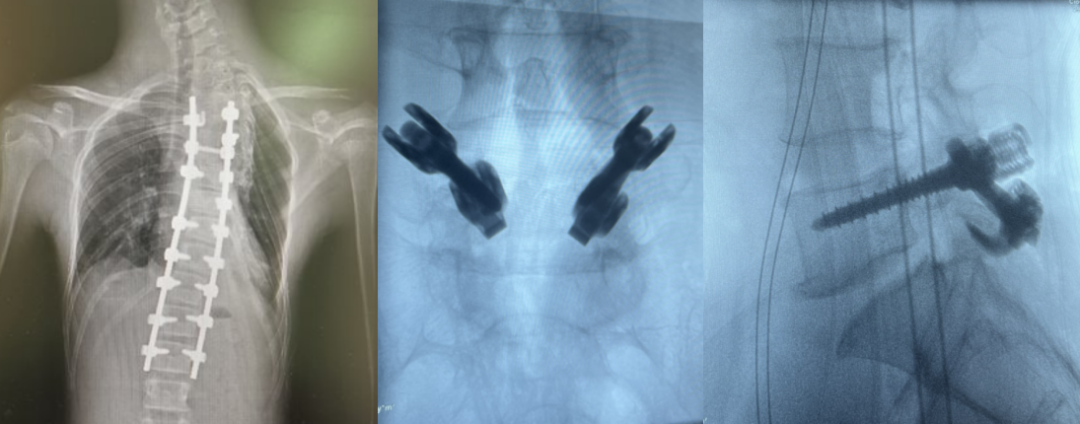

德康醫(yī)療——脊柱畸形去旋轉(zhuǎn)類方案

北京協(xié)和醫(yī)院仉建國(guó)教授團(tuán)隊(duì)合作研發(fā)的VSS脊柱專用矯形器械,功能強(qiáng)大,靈活應(yīng)對(duì)脊柱復(fù)雜三維矯形手術(shù)。

VSS惟德矯形系統(tǒng)器械常搭配單平面螺釘用于脊柱旋轉(zhuǎn)畸形患者的去旋轉(zhuǎn)操作 VSS惟德矯形系統(tǒng)器械分5.5系統(tǒng)和6.0系統(tǒng)

方案一 單平面螺釘

主要應(yīng)用于脊柱復(fù)雜畸形的矯形; 將萬向螺釘置棒容易和單軸螺釘對(duì)錐體的控制的優(yōu)點(diǎn)相結(jié)合,方便手術(shù)操作; 可精確調(diào)整螺桿高度,使螺桿與桿頭的接觸面最大化。

方案二 大偏角雙鎖緊螺釘:可單可萬向轉(zhuǎn)換

萬向大偏角,長(zhǎng)尾釘,便于置棒。

雙鎖緊機(jī)制,外鎖鎖緊,萬向釘轉(zhuǎn)為單向釘,方便矯形。

矯形完成后,內(nèi)鎖最終鎖緊,完成固定。

方案二 S2AI螺釘

專業(yè)成套工具

大偏角,U形開口,同胸腰椎后路系統(tǒng)兼容,無需其他部件,方便置棒 提供LEO-Elite&LEO-Universal系統(tǒng),滿足臨床需求 光桿設(shè)計(jì),減少骶髂關(guān)節(jié)損傷 低切跡,減少軟組織損傷